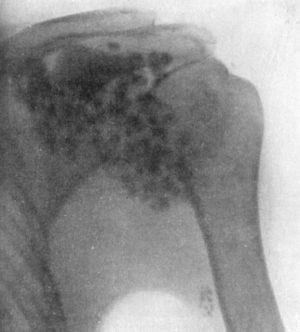

203 104.Radiogram of Specimen of Arthropathy of Shoulder in Syringomyelia

204 105.Radiogram showing Multiple partially Ossified Cartilaginous Loose Bodies in Shoulder-joint